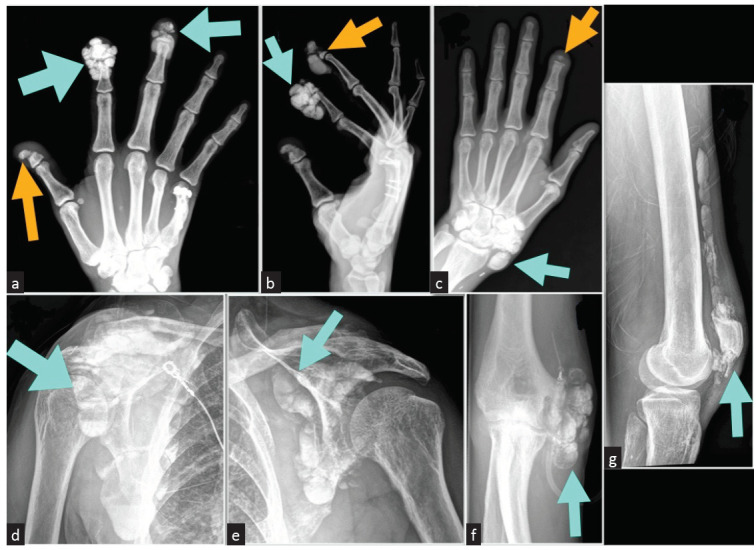

Extensive Tumoral Calcinosis and Acral Osteolysis.

广泛的肿瘤钙质沉着和肢端骨溶解。